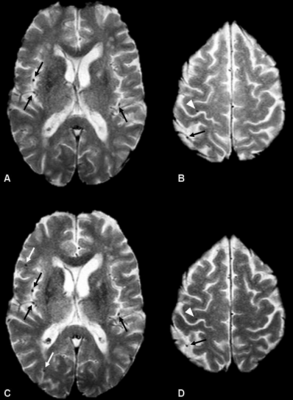

MRI Distinguishes Brain Lesions | Diagnostic Imaging

MRI Distinguishes Brain Lesions | Diagnostic Imaging from cdn.sanity.io